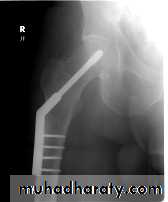

EXTERNAL FIXATIONPrinciple

IndicationsAdvantages